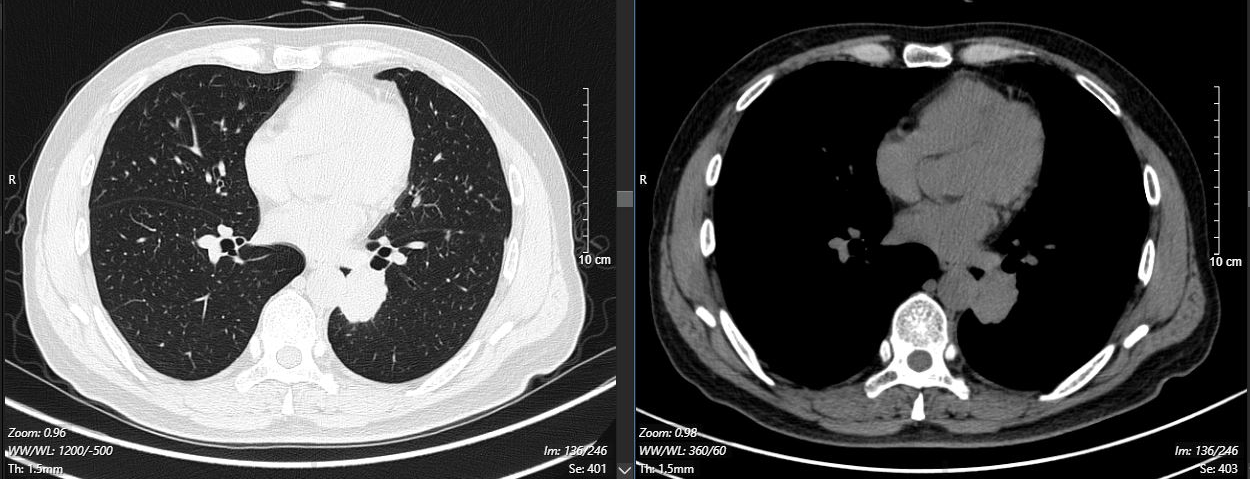

2024-11-26 胸部CT检查示:

2024-11-26 PET-CT进一步评估:左肺下叶背段近肺门处类圆形分叶状肿块(约32*28mm),FDG代谢异常增高;纵隔内4L组、左下肺门处、左侧膈肌脚内侧见稍大淋巴结FDG代谢增高,左肺内及胸膜下散在多发结节影,FDG代谢不同程度增高,考虑左肺下叶肺癌伴左肺及胸膜多发转移、多发淋巴结转移。